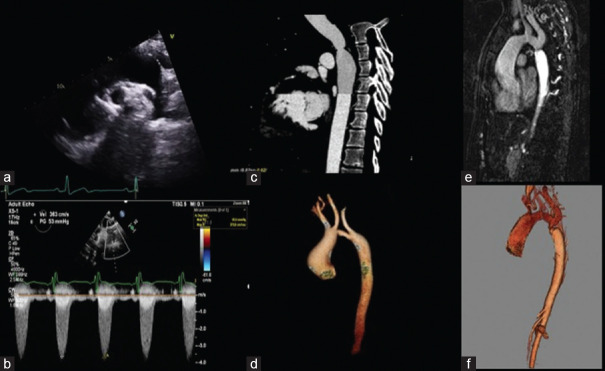

This article provides comprehensive insights into the evaluation of simple congenital heart diseases (CHDs) in adults, emphasizing the pivotal role of echocardiography. By focusing on conditions such as congenital aortic stenosis, aortic coarctation, patent ductus arteriosus, atrial septal defects (ASDs), and ventricular septal defects (VSDs), the review underscores echocardiography's intricate contributions to precise clinical decision-making. Echocardiography serves as the primary imaging modality, offering high-resolution visualization of anatomical anomalies and quantification of hemodynamic parameters. It enables tailored therapeutic strategies through its capacity to discern the dimensions, spatial orientation, and dynamic shunt dynamics of defects such as ASDs and VSDs. Moreover, echocardiography's advanced techniques, such as tissue Doppler imaging and speckle tracking, provide detailed insights into atrial mechanics, diastolic function, and ventricular filling kinetics. Integration of echocardiographic findings into clinical practice empowers clinicians to create personalized interventions based on quantified ventricular function, which spans systolic and diastolic aspects. This approach facilitates risk stratification and therapeutic planning, particularly pertinent in heart failure management within the CHD patient population. In summary, echocardiography transcends its role as an imaging tool, emerging as a precision-guided instrument adept at navigating the complexities of simple CHD in adults. Its ability to expedite diagnosis, quantify hemodynamic impacts, and unravel multifaceted functional dynamics culminates in a comprehensive depiction of these conditions. The fusion of these insights with clinical expertise empowers clinicians to navigate the intricate pathways of CHD, crafting tailored therapeutic strategies characterized by precision and efficacy.